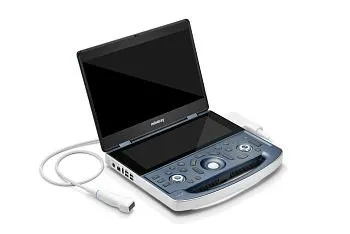

УЗИ аппарат Mindray MX7 портативный

УЗИ аппарат Mindray MX7 портативный

Mindray MX7 — высокотехнологичный портативный УЗИ аппарат, предлагающий впечатляющее качество изображения и широкий функционал. Благодаря своей компактности и мобильности, Mindray MX7 идеально подходит для работы в условиях ограниченного пространства или для выездных обследований. Портативный Mindray MX7 обладает передовыми технологиями, позволяющими получать четкие и детальные изображения в реальном времени. Благодаря различным режимам сканирования и широкому выбору датчиков, этот сканер может применяться в различных областях медицины, от акушерства и гинекологии до кардиологии и онкологии.

Приобретение УЗИ аппарата Mindray MX7 — надежное решение для клиник и врачей, которые ценят качество и точность диагностики. Надежность, мобильность и высокая производительность делают Mindray MX7 отличным выбором для специалистов, которым важны результаты и удобство работы. Вы можете заказать или купить со склада в наличии портативный УЗИ аппарат Mindray MX7 по выгодной цене, от надежного официального дистрибьютора Миндрей МСТ, с бесплатной доставкой в любой город.

Компактный дизайн и совершенная эргономика

- Вес 3 кг и толщина 44 мм (в сложенном состоянии) - сверхлегкая и тонкая портативная ультразвуковая система

- 15,6-дюймовый IPS монитор

- 12,3-дюймовый сенсорный экран обеспечивает пользователю интуитивно понятное управление

- Высокая мобильность и гибкость

Высокая автономность

Сверхдолгое время автономной работы - до 8 часов. U-bank, усовершенствованный аккумулятор, беспроводная зарядка: длительная работа и максимальное удобство.Расширенные возможности диагностики